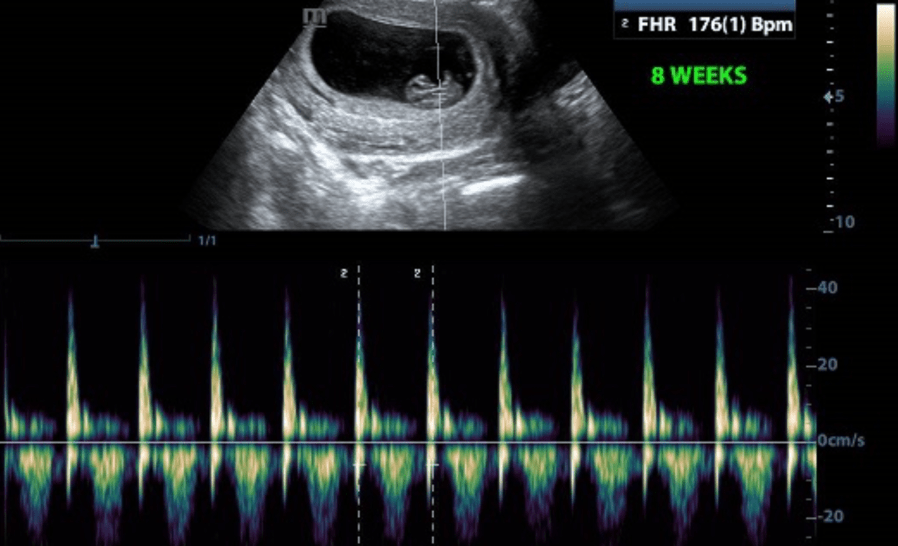

heartbeat-eight-weeks